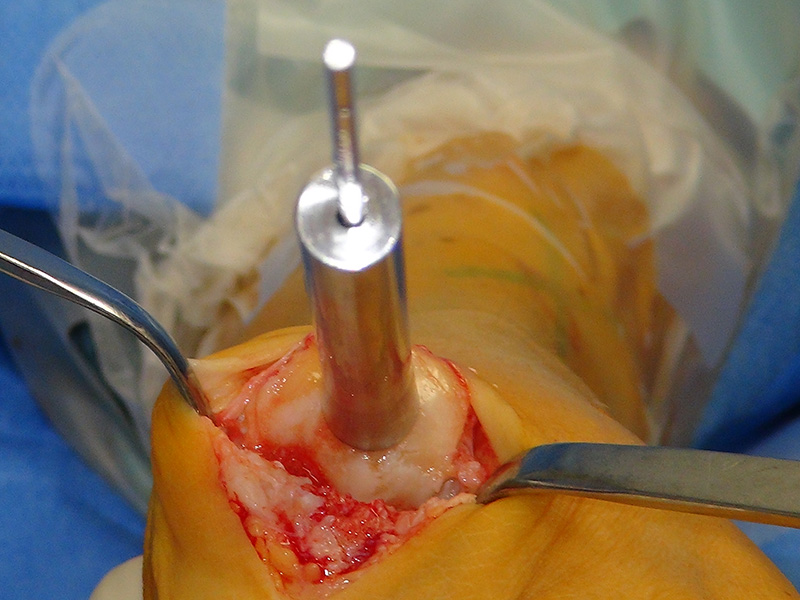

Zum Lesen der Bildbeschreibung und zur Vollansicht bitte das Bild anklicken (Foto: M. Walther).

Zum Lesen der Bildbeschreibung und zur Vollansicht bitte die Bilder anklicken (Fotos: M. Walther).